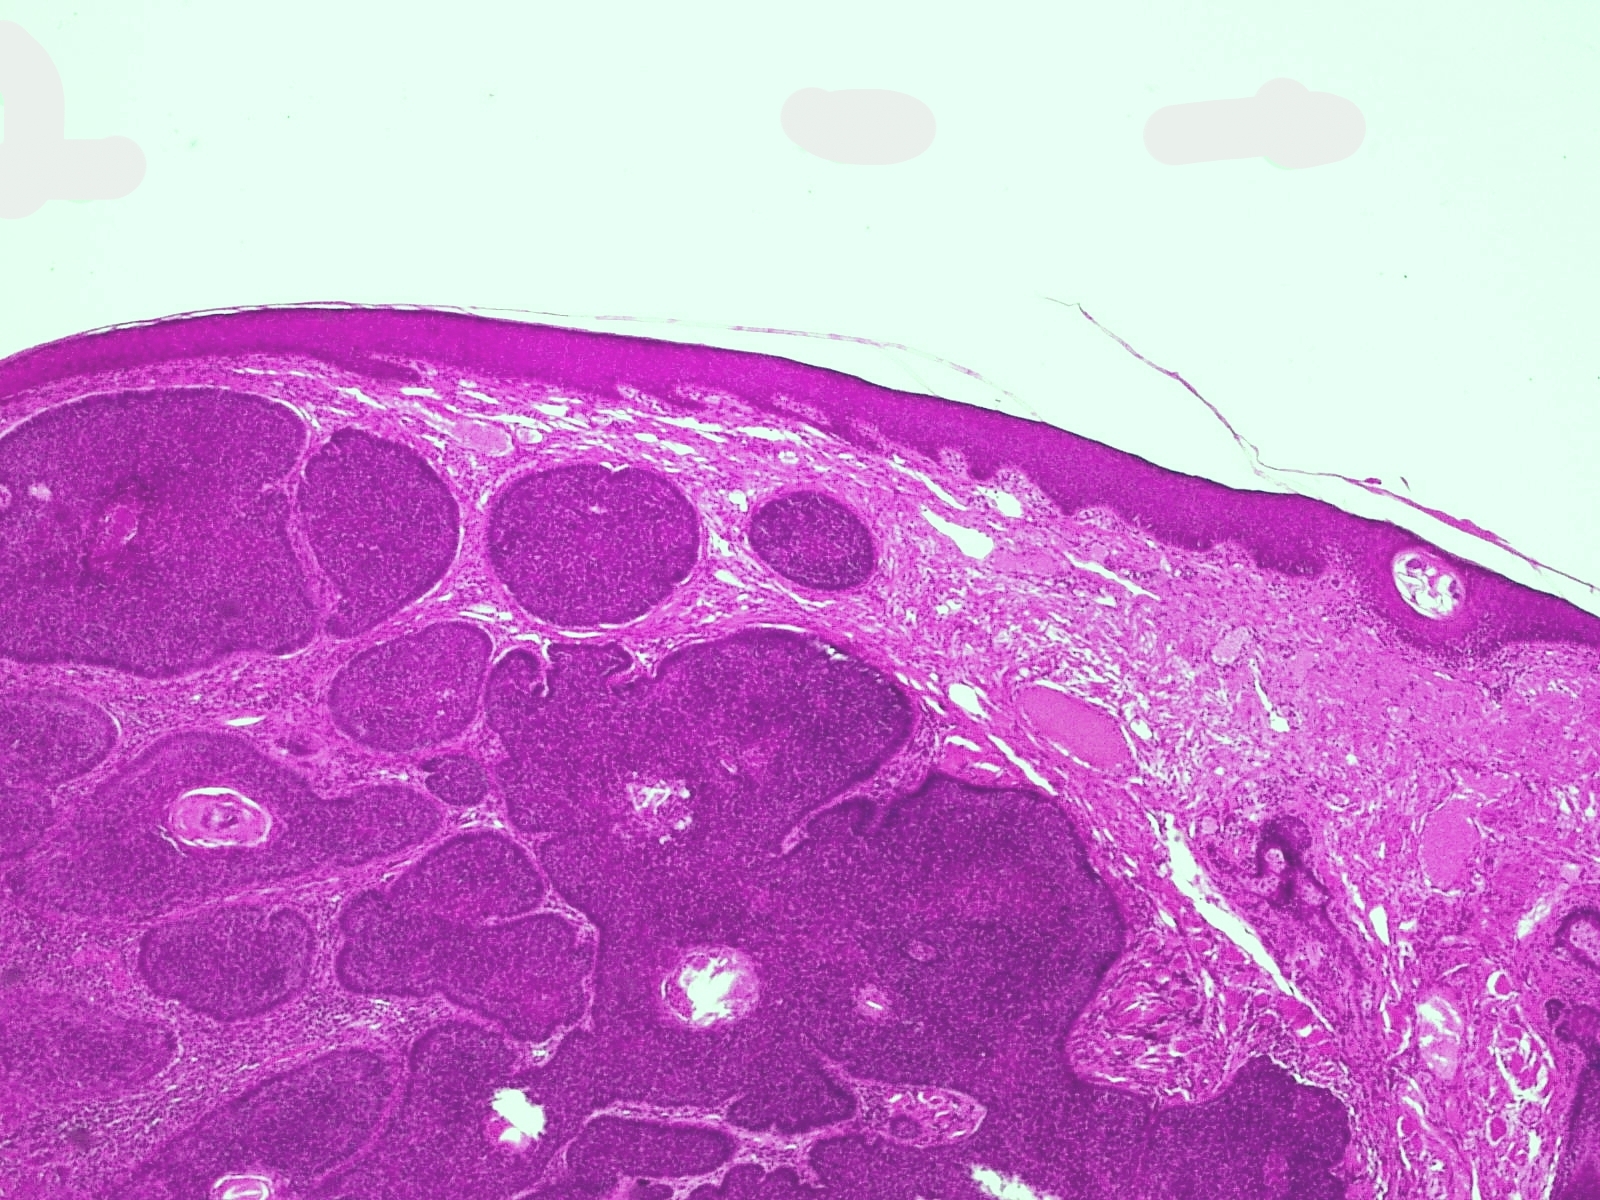

PA nodulair basaalcelcarcinoom:

Verbonden met de epidermis of de haarfollikels, soms schijnbaar zelfstandig

zonder duidelijke relatie hiermee, ziet men epitheel eilanden gekenmerkt door

donkere cellen met relatief weinig cytoplasma. De celgrenzen zijn soms niet

duidelijk en het geheel lijkt te bestaan uit een massa van donkere celkernen,

elk met een smal licht protoplasmarandje en omgeven door een rand van kernen

van hetzelfde type die als palissaden naast elkaar staan op dezelfde wijze als

in het stratum basale en rond de haarpapil. Er zijn geen celbrugjes te zien

zoals in het stratum spinosum; de door de palissadelaag ingesloten kernen lijken

wat ongeordend bij elkaar te liggen. De kernen hebben een regelmatig, uniform

aspect, ze bezitten geen anaplastische kenmerken en tonen geen abnormale mitosen.

Meestal zijn er hoorncysten in het epitheel; er is een directe overgang van

'basaloide' cellen in hoorn en niet, zoals in de epidermis, via voorstadia zoals

stratum spinosum of stratum granulosum. Deze hoorncysten komen voor bij vrijwel

alle vormen en varianten van het carcinoma basocellulare, soms echter vormen

ze een hoofdkenmerk. Het bindweefsel in de cutis blijkt in relatie tot de tumorcellen

mee te groeien, er is geen infiltratieve groei. Dit blijkt o.a. uit het feit

dat zich bij de fixatie vaak spleten vormen op de grens van carcinoom-bindweefsel,

een verschijnsel dat niet bij carcinoma spinocellulare (waarbij wel infiltrerende

groei plaatsvindt) te zien is. Het bindweefsel rond de tumorveldjes bevat vele

jonge fibroblasten en is hier bovendien metachromatisch (zure mucopolysacchariden)

en PAS-positief als bij de haarpapillen. De vaten zijn toegenomen en verwijd;

er is soms opvallend weinig cellulair infiltraat. Soms echter bevindt zich,

vooral vlak bij de tumorveldjes, enig lymfocytair infiltraat. Is ulceratie opgetreden

dan neemt het infiltraat toe en bevat het aan de oppervlakte soms talrijke polynucleaire

granulocyten. Carcinoma basocellulare komt niet aan de slijmvliezen voor. Zie